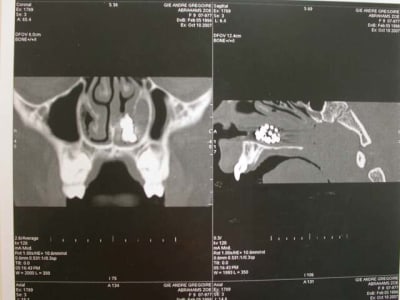

l'objet: une petite chainette boule métallique (celles qui sont accrochées à certains vetements et qu'on retrouve sur les bouchons de baignoire) complétement oxydée (noir de chez noir, avec diminution du diametre de certaines boules) .

temps de séjour estimé dans les fn: 4-5 ans

La maman de zoe vient en consultation, pour un contrôle semestrielle. Elle est enceinte de 8 mois, se porte bien , et rien de particulier ne doit être entrepris avant la fin de la grossesse. En fin de rendez-vous, elle me demande de jeter un œil sur Zoe. La petite agée de 9ans et demi présente une jolie classe III osseuse. J’en profite pour lui faire une panoramique. Là, à ce stade, vous avez tous vu le résultat. Je vérifie qu’il ne reste pas une barrette oubliée ou autre (nada), et préfère effectuer une nouvelle pano. Même résultat.

Je questionne l’ enfant et la maman. Personne ne se rappelle de rien. Je me renseigne s’il n’y a pas eu une intervention chirurgicale, et le seul antécédent est une opération pour ôter les végétations, il y a 4 ans. J’examine le nez et ne vois rien. Je pense plus à un objet oublié pendant l’intervention.

Je décide donc de faire réaliser un scanner et là c’est nouveau pour vous.

Une fois le scanner réalisé, je vois bien qu’il s’agit d’un objet composé de boules et l’adresse illico à son orl. Il la reçoit dans la foulée, et au vu du scanner, se refuse d’intervenir de peur de renvoyer plus loin l’objet. A son tour, il l’adresse à un hopital spécialisé enfants (Robert Debré). Au service ORL, ils tentent de retirer l’objet avec une pince (comme Dr House le faisait dans un épisode) et rien de neuf, aucune progression.